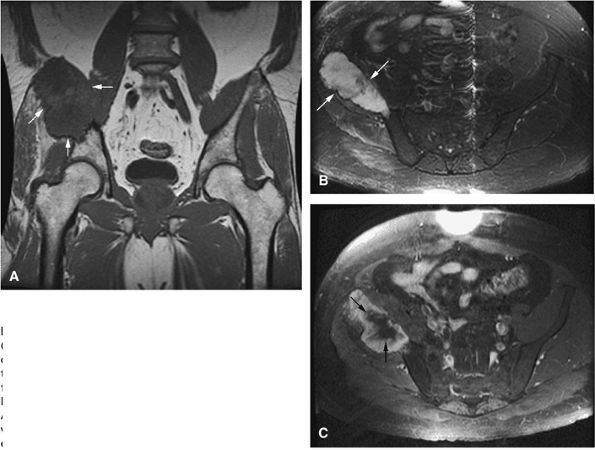

FIGURE 14-88 ● Metastatic thyroid cancer. (A) An anteroposterior radiograph shows cortical destruction and a large lytic lesion of the iliac wing (arrows). Axial CT scans (B and C) show destruction of the left iliac wing with a large associated soft-tissue mass (arrows). On coronal T1-weighted (D) and axial proton density-weighted (E) images, the low- to intermediate signal-intensity metastatic tumor and soft-tissue mass are noted (arrows). On the corresponding axial (F) and sagittal (G) STIR images, the metastatic tumor (arrows) demonstrates intermediate signal intensity, with central areas of fluid signal, indicating necrosis. (H) The axial fat-suppressed T1-weighted image following administration of intravenous gadolinium shows central nonenhancing areas, indicating necrosis (arrows).